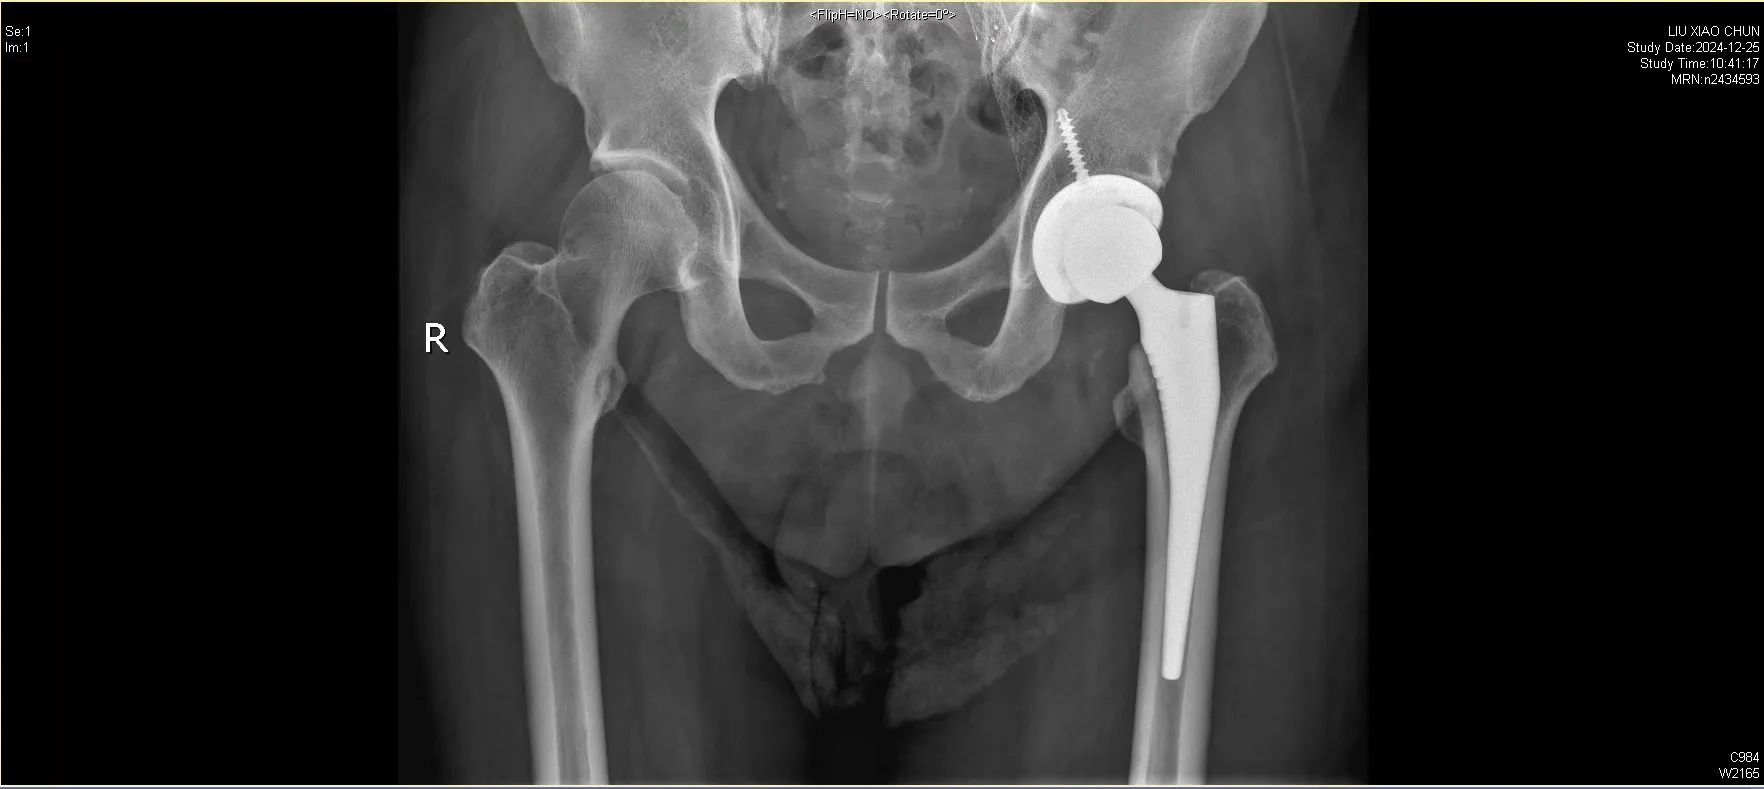

50 多岁的患者刘先生(化名),体重200斤,卧床半年多,肝硬化、冠心病、重症感染各种疾病缠身。

面对这位重度肝硬化合并多器官功能不全、髋部感染的患者,我院骨科与运动医学中心徐杰教授、邱美光主任及其团队成功为他实施关节置换手术。

患者刘先生患有酒精性肝硬化,并发脾功能亢进、血小板减少症、门静脉高压,以及肺动脉高压、慢性阻塞性肺疾病等多种严重基础疾病。同时,刘先生的髋部也遭受感染,患上感染性髋关节炎,还伴有左股骨头坏死。

在各学科专家的共同努力下,徐杰教授及邱美光主任的关节外科团队,经过细致的术前评估,为患者制定了周密的手术方案:1.先改善多器官功能及血小板功能;2.手术分期进行:一期处理髋部感染病灶、 切除坏死股骨头;二期成功实施髋关节置换术。

手术过程顺利,术中生命体征平稳,术后由多学科团队联合管理,康复团队为患者量身定制了个性化康复计划。在医护人员的精心照护下,患者恢复迅速,术后第二天即借助助行器成功下地行走。